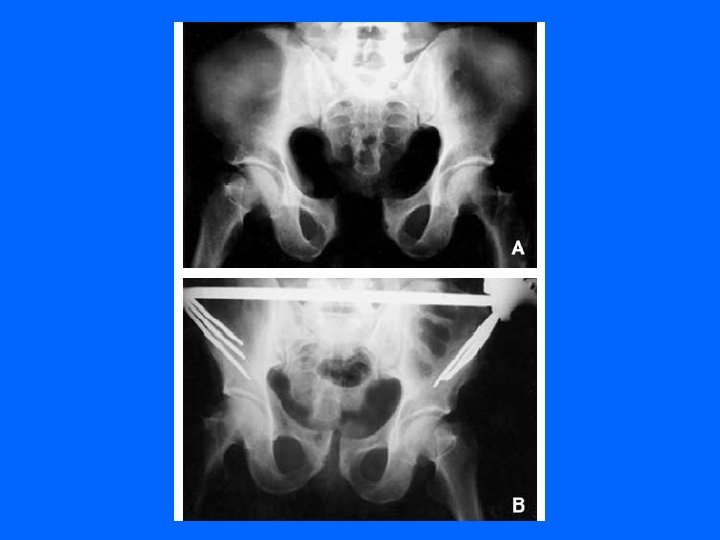

Trt Orthopédique Le décubitus sur hamac Disjonction pubienne ou postérieure sans déplacement

La suspension-traction Hamac + traction pour réduire un cisaillement vertical traction par une broche trans-condylienne si déplacement vertical.

Fixateur externe : stabilise rapidement et sans ouvrir les disjonctions antérieures et postérieures. permet de traiter tout de suite les lésions associées